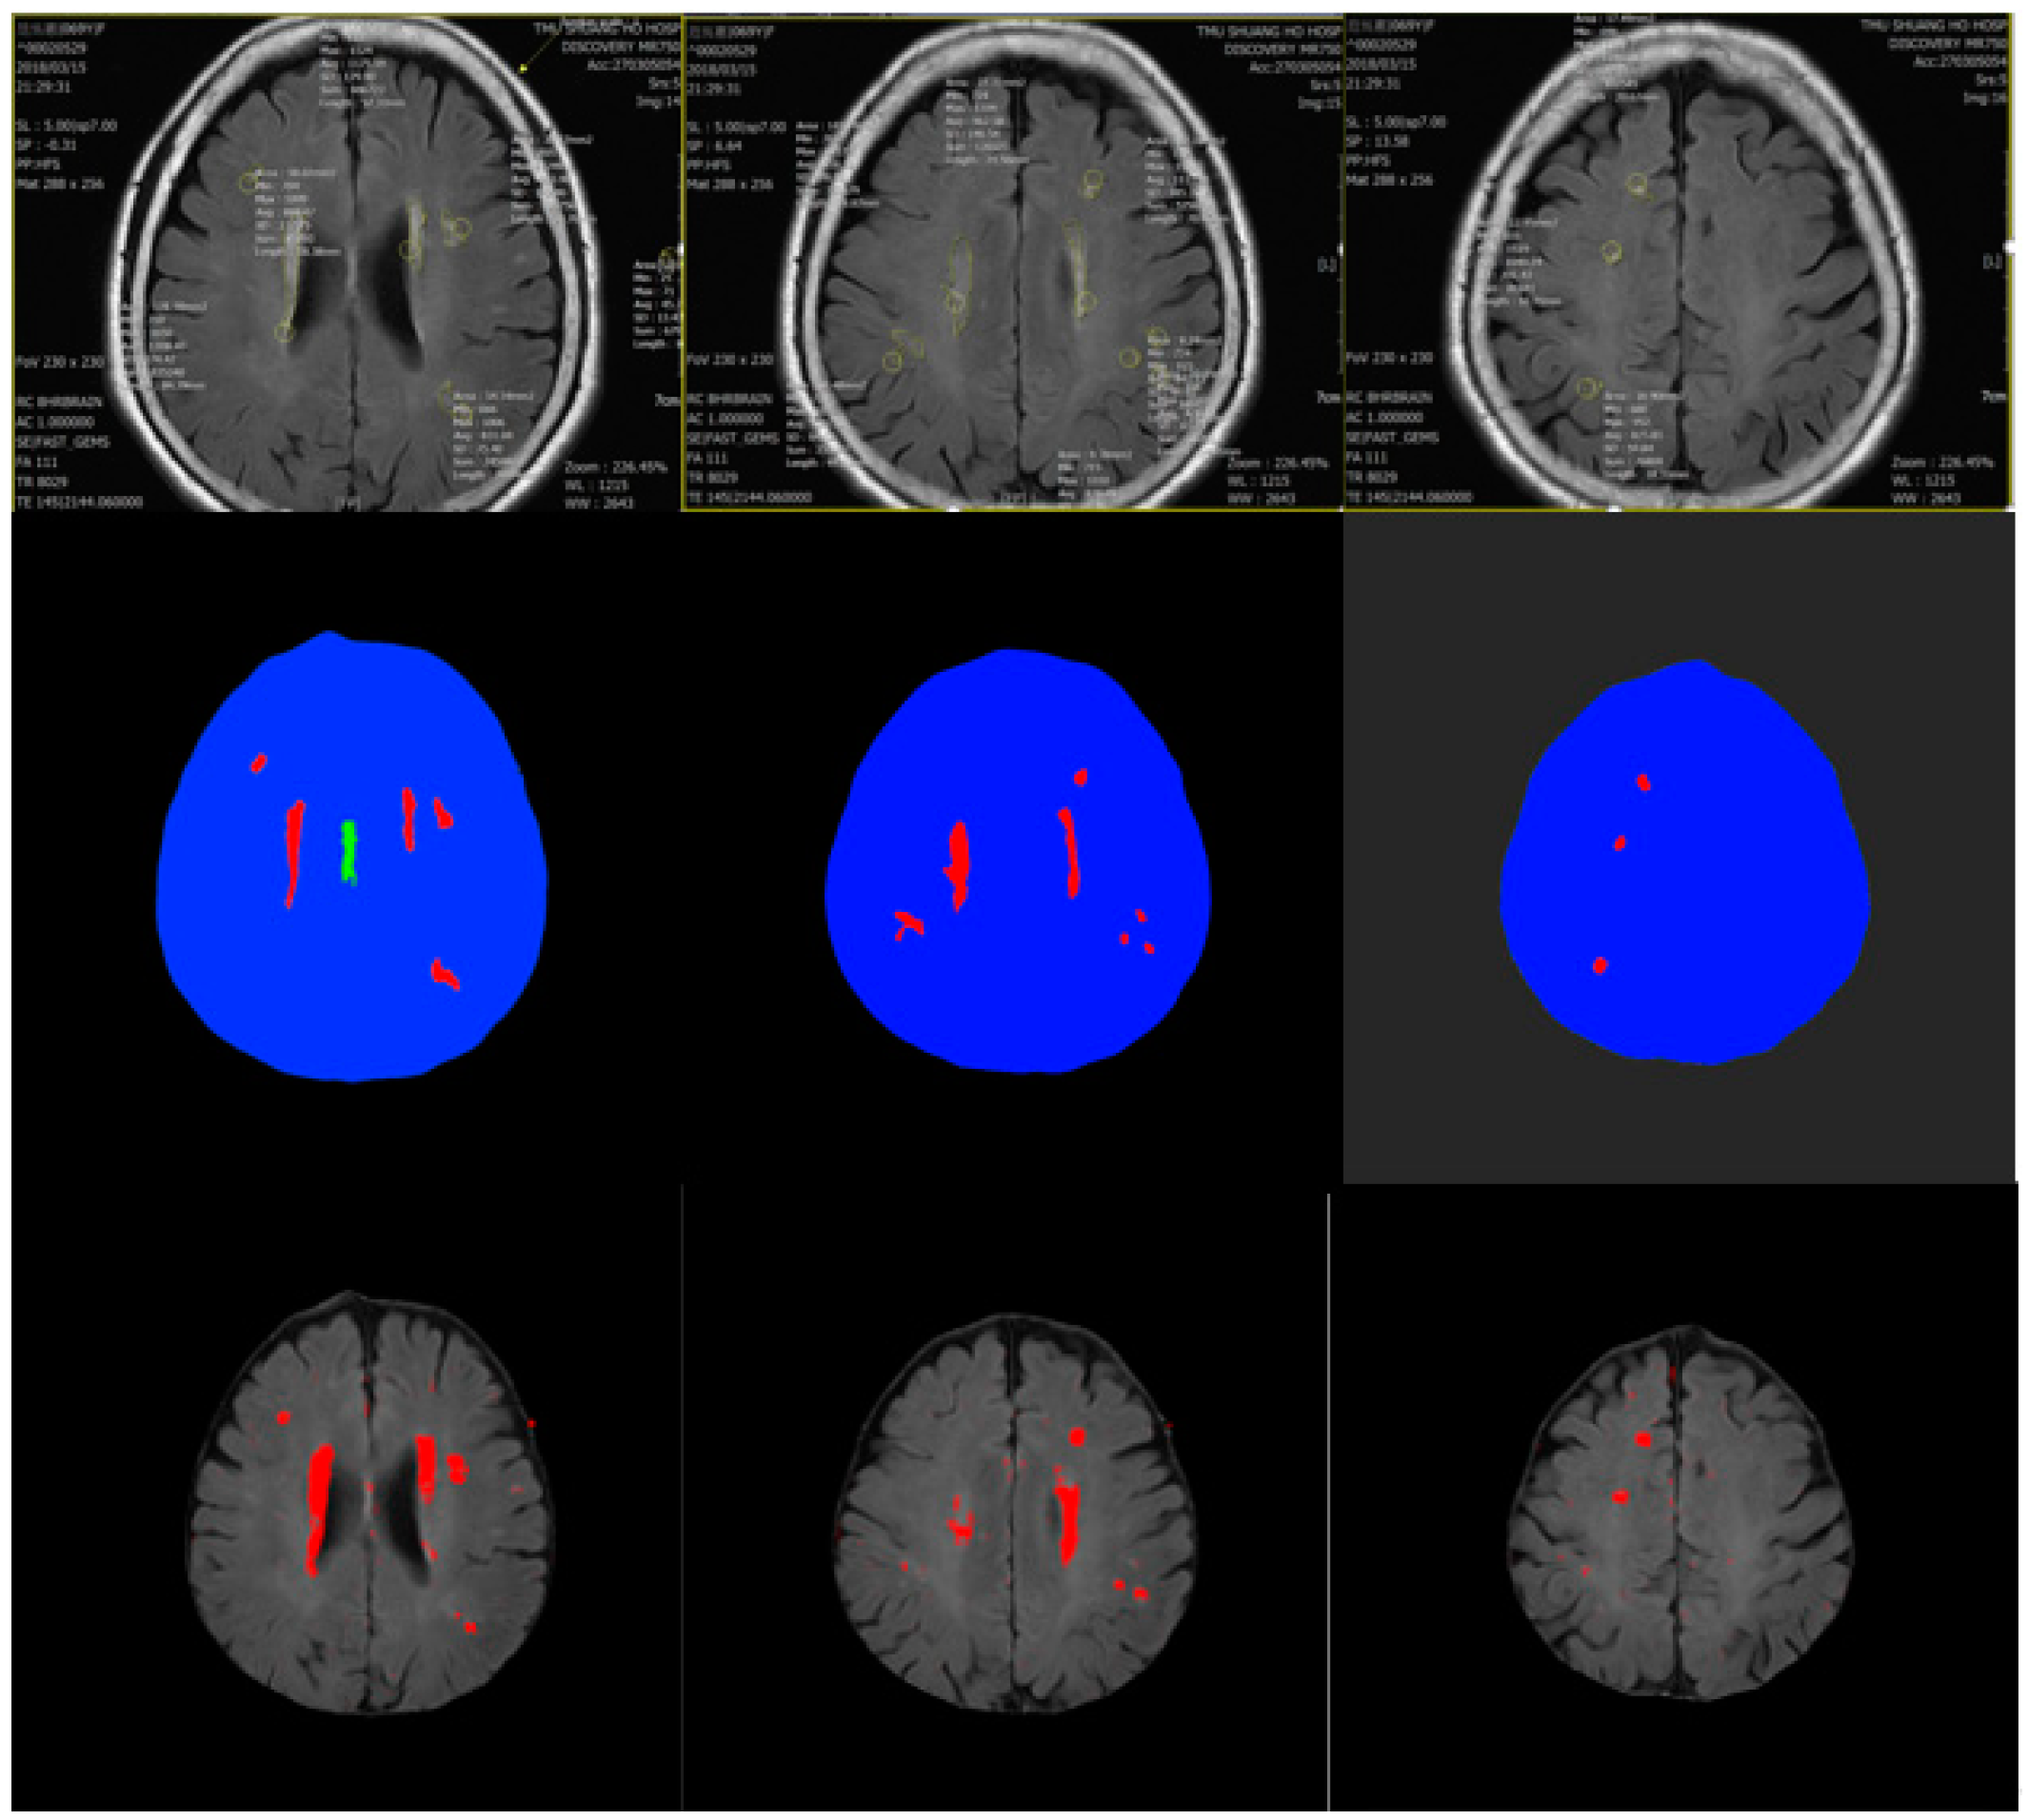

3.1. Data Preprocessing

3.2. Training Model

4. Experiment Results

Comparison with Other Training Models